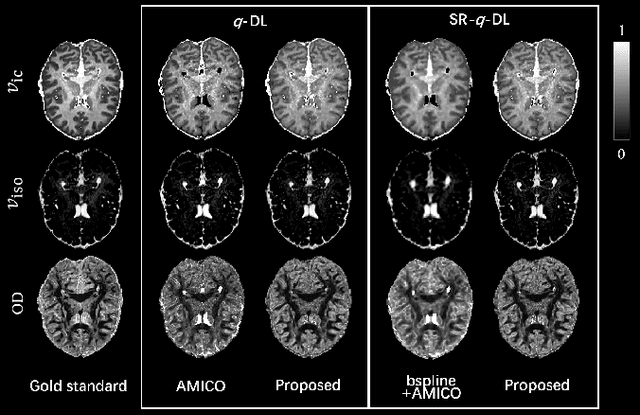

Abstract:Learning-based approaches, especially those based on deep networks, have enabled high-quality estimation of tissue microstructure from low-quality diffusion magnetic resonance imaging (dMRI) scans, which are acquired with a limited number of diffusion gradients and a relatively poor spatial resolution. These learning-based approaches to tissue microstructure estimation require acquisitions of training dMRI scans with high-quality diffusion signals, which are densely sampled in the q-space and have a high spatial resolution. However, the acquisition of training scans may not be available for all datasets. Therefore, we explore knowledge transfer between different dMRI datasets so that learning-based tissue microstructure estimation can be applied for datasets where training scans are not acquired. Specifically, for a target dataset of interest, where only low-quality diffusion signals are acquired without training scans, we exploit the information in a source dMRI dataset acquired with high-quality diffusion signals. We interpolate the diffusion signals in the source dataset in the q-space using a dictionary-based signal representation, so that the interpolated signals match the acquisition scheme of the target dataset. Then, the interpolated signals are used together with the high-quality tissue microstructure computed from the source dataset to train deep networks that perform tissue microstructure estimation for the target dataset. Experiments were performed on brain dMRI scans with low-quality diffusion signals, where the benefit of the proposed strategy is demonstrated.